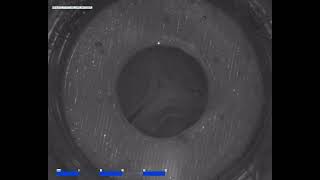

A polymeric heart valve prototype in the pulse duplicator video

A polymeric heart valve prototype in the pulse duplicator

A polymeric heart valve prototype in the pulse duplicator Polymeric Heart Valve in the Pulse Duplicator System

A polymeric heart valve prototype in the pulse duplicator

A polymeric heart valve prototype in the pulse duplicator Polymeric Heart Valve in the Pulse Duplicator System